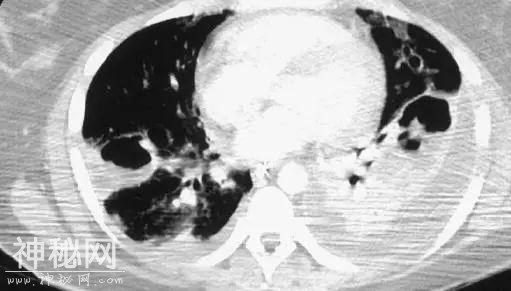

■ CT特点:

1.双肺多发气囊、空洞,斑片影;

2.病灶以胸膜下为主。

■ 诊断

像这样的CT,这样的患者,绝大多数都是金黄色葡萄球菌(以下简称“金葡菌”)感染!